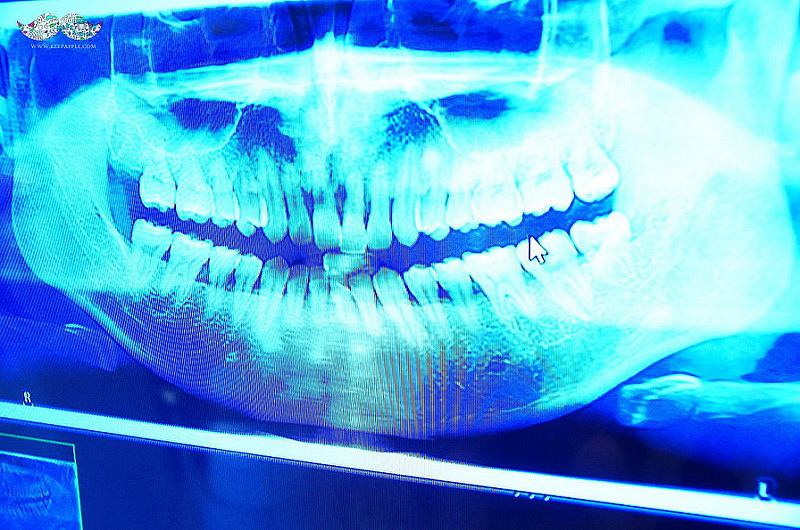

第一次看牙檢查

抱著非常戒慎的表情,

去照了全口X光機;

外表看不出來,

但害怕的內心已經翻了幾翻....

因為牙周病的關係,

已經有一顆門牙晃動而且跑出來。

其它部分牙齦也腫脹,

其實已經是很嚴重的。

結果院長曹醫師來啦!!!

用X光片解說目前我的牙齒狀況,

以及如何進行治療的說明~

仔細檢查了之後,

沒錯,小逼的牙真的爛到不行,

因為拖太久沒在管。

為了更清楚地確認牙根部分的恢復情況,

所以再照一次X光機,

來決定這次治療需要的程序~